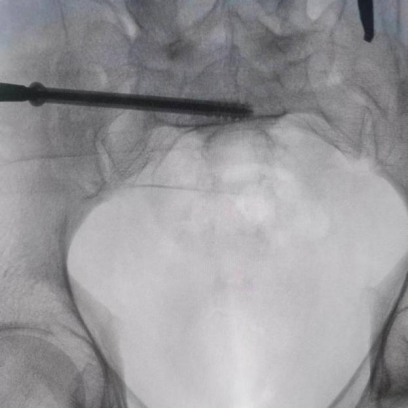

據(jù)了解,患者37歲,為高墜傷患者,入院合并顱腦挫傷、盆腔臟器出血、骨盆骨折多發(fā)傷患者。為最大限度降低手術(shù)風險,同時給予患者滿意的手術(shù)療效,術(shù)前綜合評估患者病情,擬定行“天璣機器人”輔助定位下骨盆骨折微創(chuàng)手術(shù)。2月13日10時,手術(shù)正式開始。拉薩市人民醫(yī)院采集患者術(shù)中二維影像,通過骨科手術(shù)機器人擬定螺釘打入位置方向后,吳宏華主任完成手術(shù)設(shè)計,成功為該患者置入了一顆高難度骶髂螺釘,出血5ml,切口1cm。術(shù)后圖像顯示,螺釘位置及方向完全符合手術(shù)規(guī)劃,沒有一絲偏差,手術(shù)最終獲得圓滿成功。

圖為透視下見置入的骶髂螺釘,位置、長度精準,無絲毫偏差